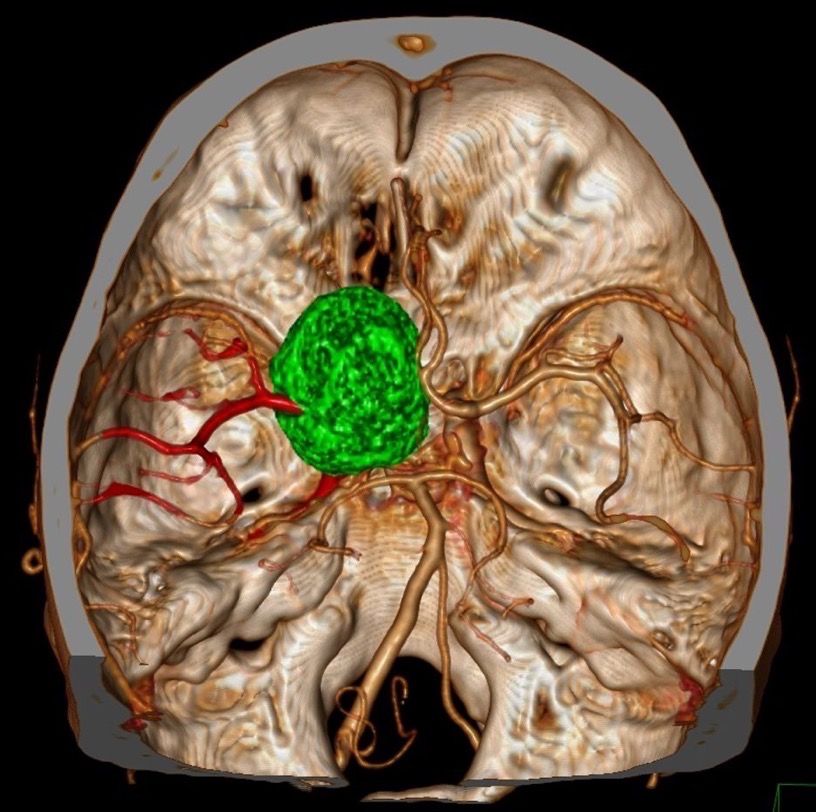

CTA血管造影及三维重建: